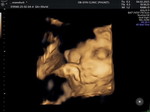

อายุครรภ์ 37 weeks